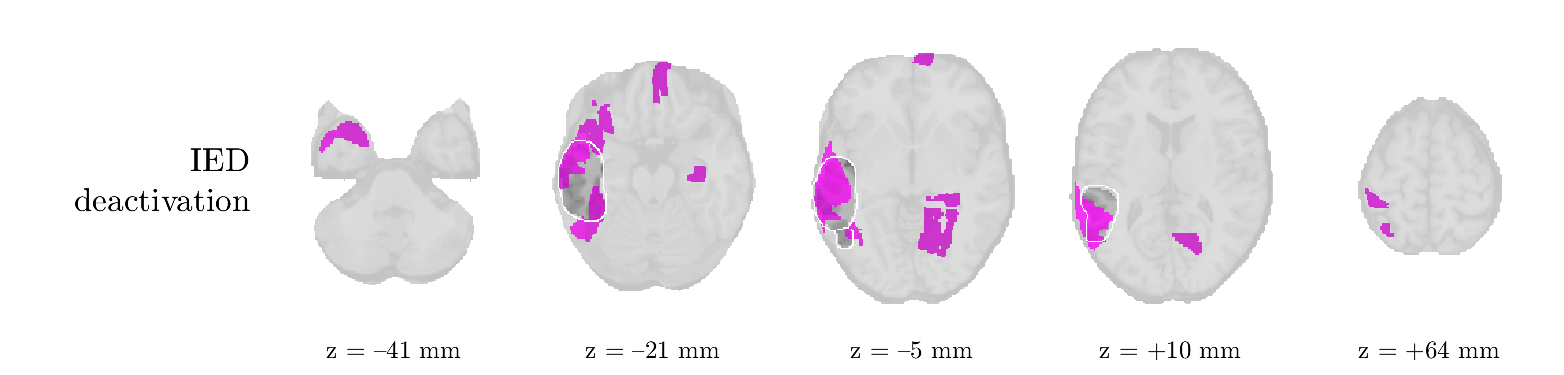

Patient 2

We analyze the solution with sources, and show the results in Figure 3 and 4. As for patient 1, we found a source which is strongly correlated to the MWF envelope, and which had a mostly low-frequency behavior characteristic for spikes. The topography is mostly uninformative, and does not clearly correspond to the patient’s clinical data. The third source is mostly present at both sides of the head, is very sparsely active in time, and has a high-frequency content: this is most likely an artifact due to the neck muscles. Again, there is one of the highest-entropy HRFs which belongs to a ROI in the IOZ. Now, the waveform is clearly resolved from the other HRFs, through the strong initial dip (before 0 seconds). Such a dip is sometimes observed in HRFs, but its underlying physiological mechanism is not yet fully understood. It is possible that this dip reflects altered vascular autoregulation near the IOZ (cfr. the explanation in the Section 1 of the main text), or a rapid depletion in oxygen due to IED generation (before the IED becomes visible on the EEG). Figure 4 furthermore shows that the IED-related component is significantly active in parts of the IOZ, and deactive in others. As mentioned earlier, this deactivation may or may not be due to errors in sign correction. Interestingly, the ROI with the high alteration in neurovascular coupling is distinct from both the activated and deactivated ROIs.